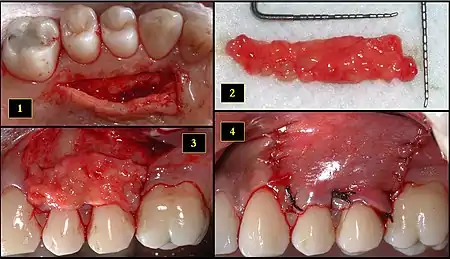

1. Ipsilateral palatal mucosa serving as the donor site

2. The retrieved connective tissue, approximately 25 × 6 mm in dimension

3. Connective tissue placed at recipient site

4. Recipient site flap coronally advanced and sutured to entirely cover the graft